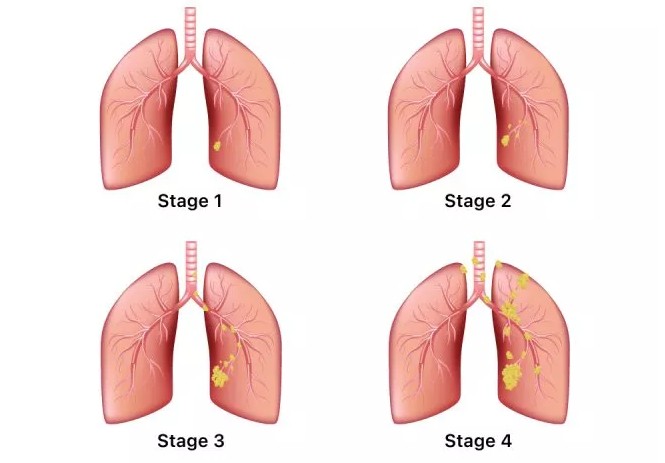

폐암은 위암, 갑상선암 다음으로 3번째로 발병 빈도가 높은 3대 암 중 한 가지인데요. 폐암은 재발과 전이까지의 빈도도 잦은지라 완치가 어렵다고 하며 폐암 발병 초기에는 거의 증상이 없을 수가 있어 수술이 불가능한 3기, 혹은 4기에 주로 진단된다고 해요.

폐암 초기증상 폐암 4기에 이르게 되면 5년 생존률이 30% 대로 감소하게 된다고 해요. 그리하여 폐암은 암 질병이자 중 사망자 비율이 가장 높은 것으로 나타나고 있어요.